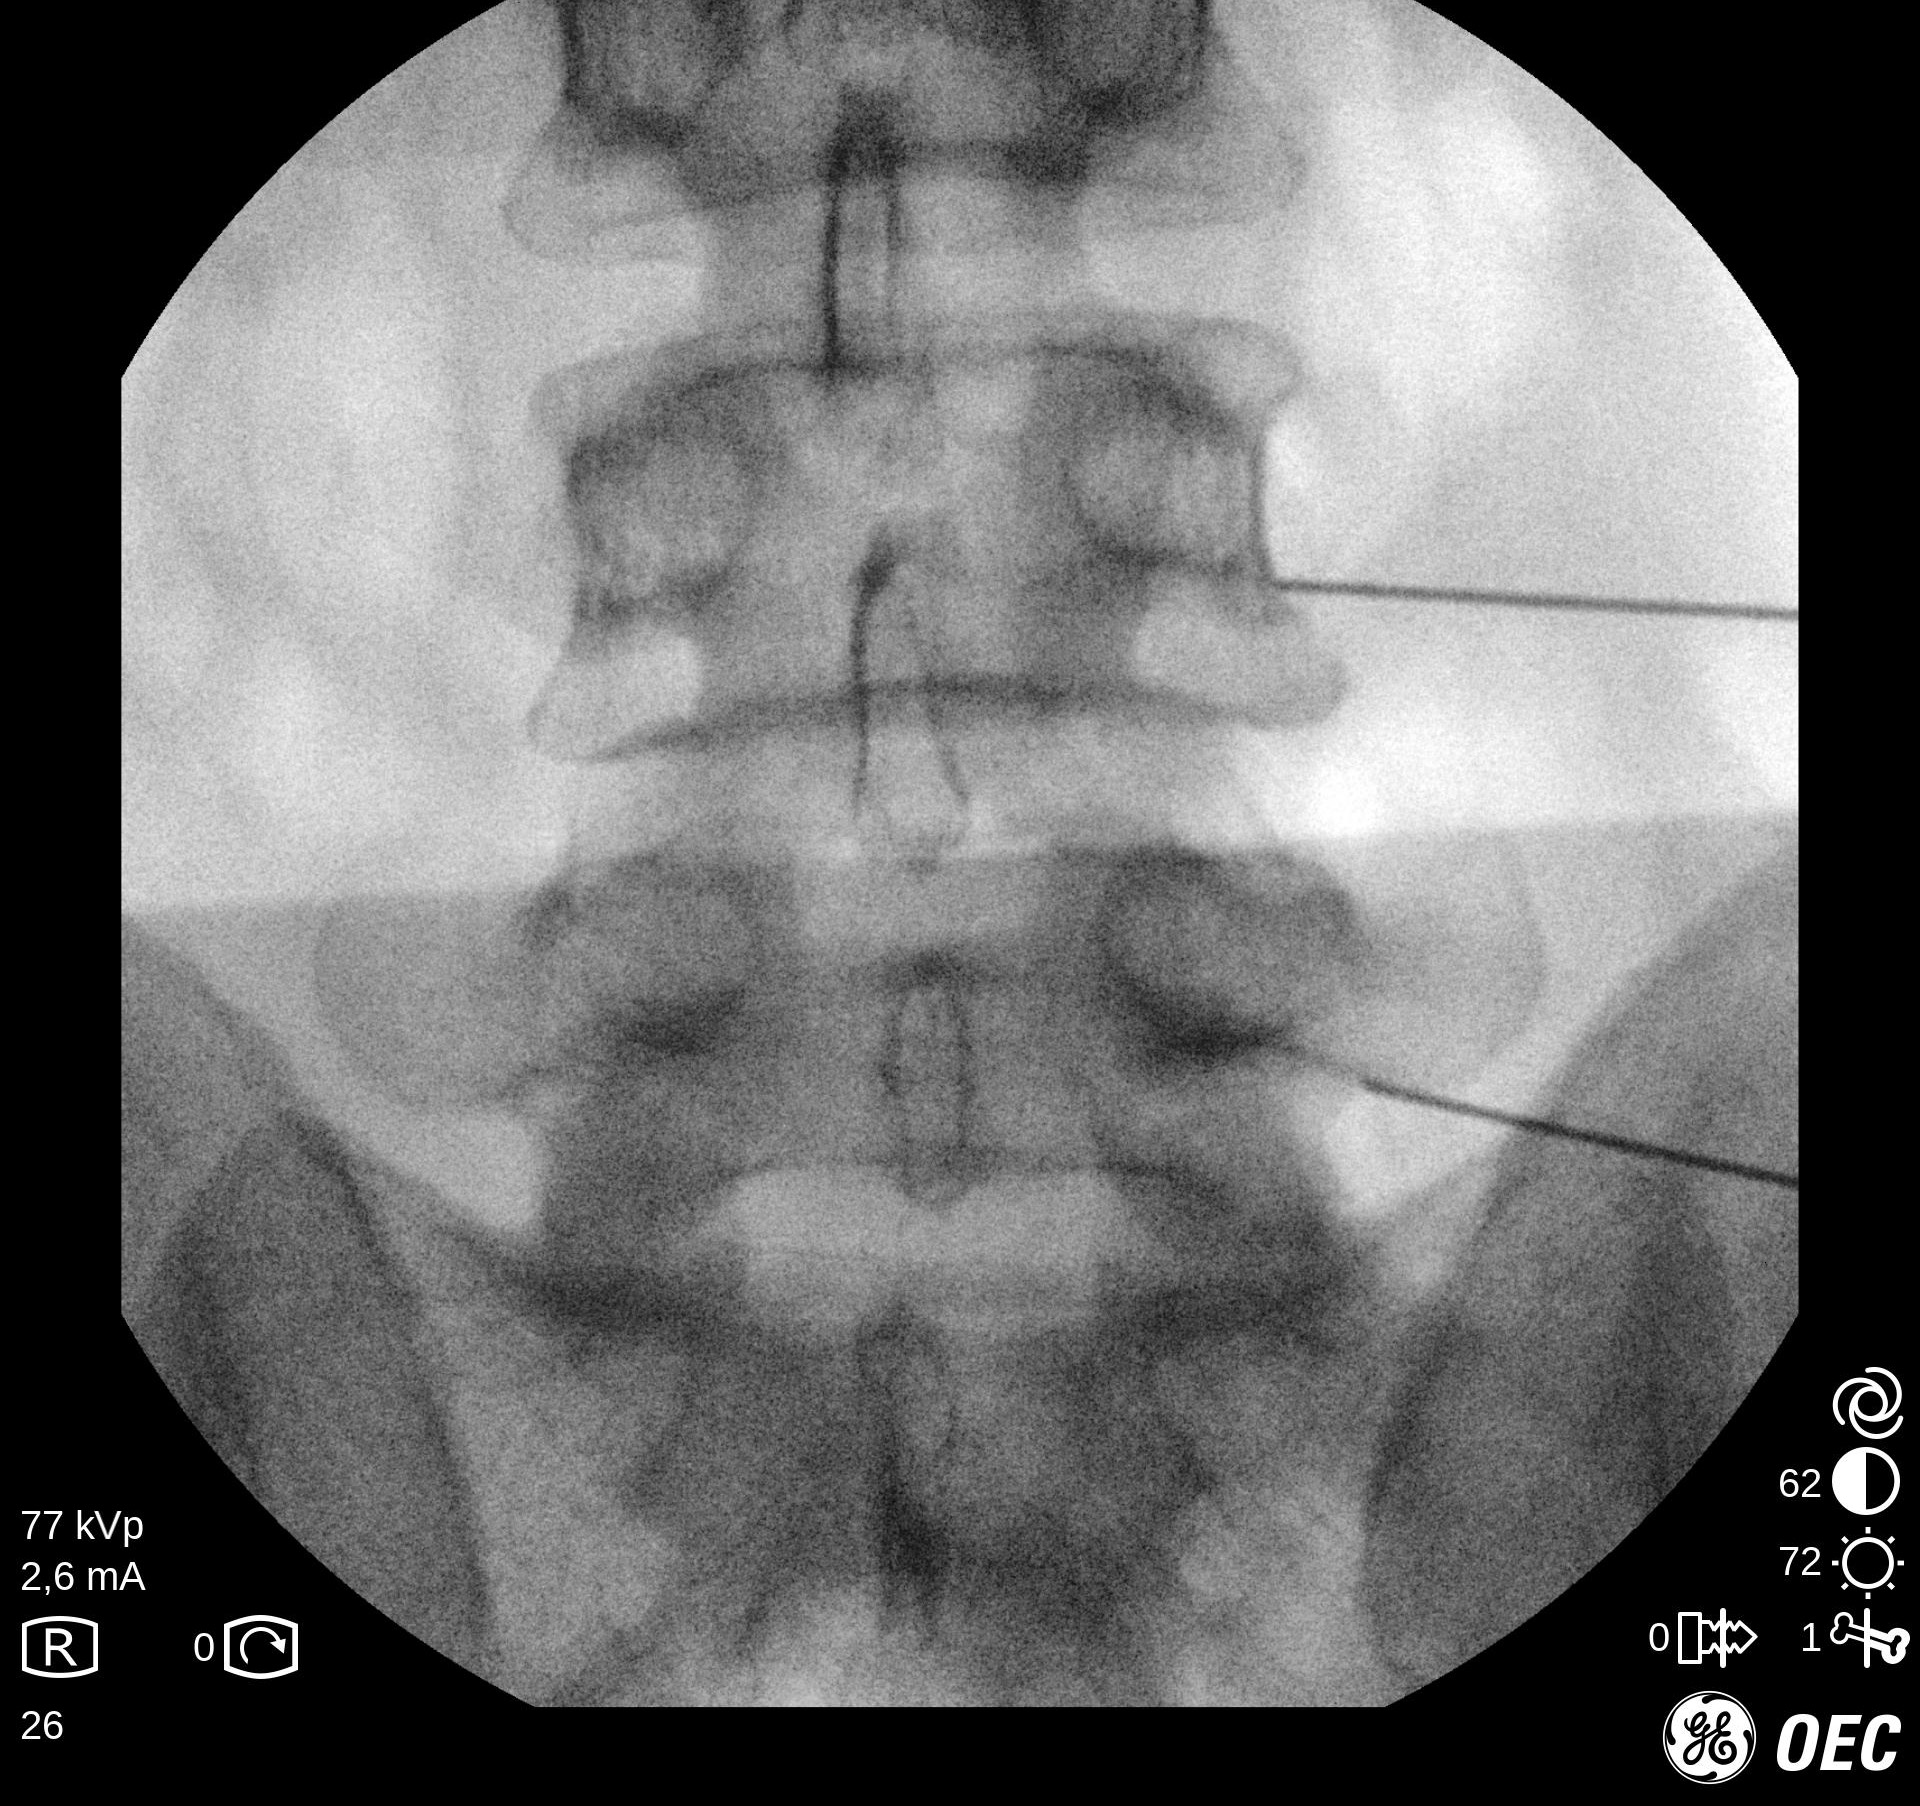

Ασθενής με άλγος οσφύος και ισχίου

Ασθενής 75 ετών με έντονο άλγος οσφύος και ισχίου από 8μήνου. Υπεβλήθη σε πλήθος απεικονιστικών και εργαστηριακών εξετάσεων με διάφορες θεραπείες που αφορούσαν την περιοχή του ισχίου αλλά χωρίς αποτέλεσμα. Απευθύνθηκε στο κέντρο μας και πραγματοποιήθηκε έγχυση σε 3 επίπεδα με άμεση ανακούφιση. Η ασθενής 1 μήνα μετά βαδίζει ελέυθερα χωρίς πόνο.